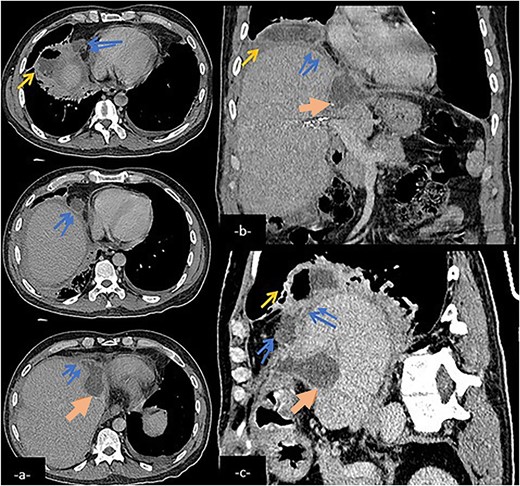

Abdominal CT scan in axial (a), coronal (b), and sagittal (c) reconstruction showing a biliary collection (large arrow) in the left hepatic lobe communicating with a subphenic and pleural collections with possible connexion with lower right airways (arrow) via a fistulary tract (double arrow).